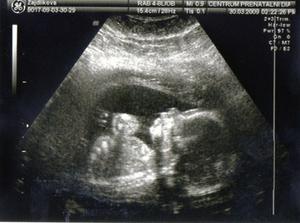

4.2. NT screening.Ultrazvuk dopadl na 1.Ještě čekáme na výsledky krve.Ty by měly být v poradně 19.2.Snad bude i tady vše v pořádku.Máme strach.***********************19.2.odběry na NT screening dopadl na 1.Tak aspoň něco.Na ultrazvuku je mimi o něco menší,ale snad to nebude nic znamenat.Příští týden na krev na TT. 19.3. další poradna.A pak se už pojede do Brna na velký ultrazvuk.***********************************30.3. velký ultrazvuk v brně.Držte nám pěsti,ať je vše OK.****************************************30.3. ultrazvuk v brně dopadl na 1.Mimi je v pořádku a hlavně,čekáme HOLČIČKU.******************************************************************************